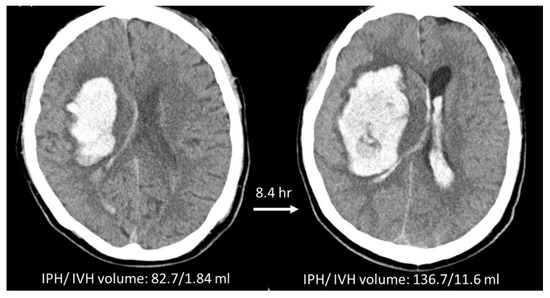

2.5. Manual Hematoma Segmentation and HE Definition